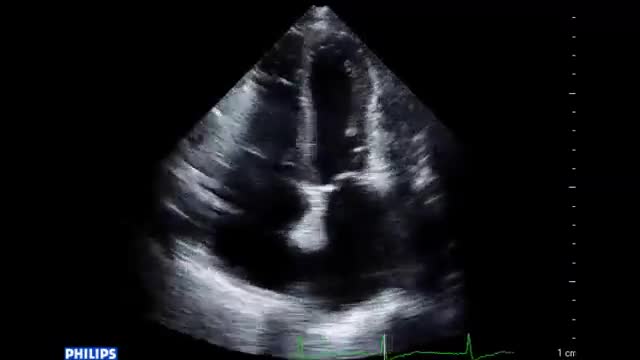

• 図5 心エコー、手術所見 a

図5 心エコー、手術所見 a